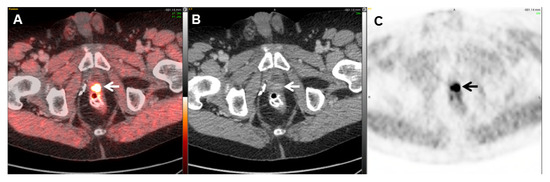

- Kroenke, M.; Schweiger, L.; Horn, T.; Haller, B.; Schwamborn, K.; Wurzer, A.; Maurer, T.; Wester, H.J.; Eiber, M.; Rauscher, I. Validation of 18F-rhPSMA-7 and 18F-rhPSMA-7.3 PET Imaging Results with Histopathology from Salvage Surgery in Patients with Biochemical Recurrence of Prostate Cancer. J. Nucl. Med. Off. Publ. Soc. Nucl. Med. 2022, 63, 1809–1814. [Google Scholar]

- Jani, A.B.; Ravizzini, G.C.; Gartrell, B.A.; Siegel, B.A.; Twardowski, P.; Saltzstein, D.; Fleming, M.T.; Chau, A.; Davis, P.; Chapin, B.F.; et al. Diagnostic Performance and Safety of 18F-rhPSMA-7.3 Positron Emission Tomography in Men with Suspected Prostate Cancer Recurrence: Results From a Phase 3, Prospective, Multicenter Study (SPOTLIGHT). Reply. J. Urol. 2023, 210, 411–412. [Google Scholar] [CrossRef]

- Jani, A.B.; Ravizzini, G.C.; Gartrell, B.A.; Siegel, B.A.; Twardowski, P.; Saltzstein, D.; Fleming, M.T.; Chau, A.; Davis, P.; Chapin, B.F.; et al. Diagnostic Performance and Safety of 18F-rhPSMA-7.3 Positron Emission Tomography in Men with Suspected Prostate Cancer Recurrence: Results From a Phase 3, Prospective, Multicenter Study (SPOTLIGHT). J. Urol. 2023, 210, 299–311. [Google Scholar] [CrossRef]

- Chantadisai, M.; Buschner, G.; Kronke, M.; Rauscher, I.; Langbein, T.; Nekolla, S.G.; Schiller, K.; Heck, M.M.; Maurer, T.; Wurzer, A.; et al. Positive Predictive Value and Correct Detection Rate of 18F-rhPSMA-7 PET in Biochemically Recurrent Prostate Cancer Validated by Composite Reference Standard. J. Nucl. Med. Off. Publ. Soc. Nucl. Med. 2021, 62, 968–974. [Google Scholar]